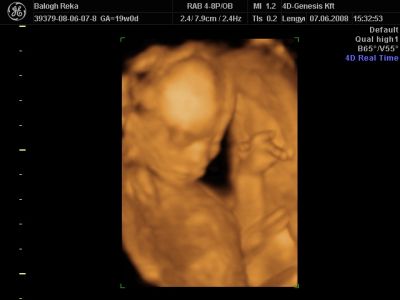

Huhh, hát annyira jó élmény volt, most tök boldog vagyok! Nagyon örülök, hogy mégis elmentem mégegyszer, mert sokat vacilláltam ám. A 4D Genesis egyszerűen szuper, mindenkinek nagyon nagyon tudom ajánlani, ezen belül is engem a Lengyel Györgyné Márti fogadott. Szuper ez a nő, akkora átéléssel és profizmussal csinálta az egész vizsgálatot! Mindent részletesen megnézett, megmutatott, elmagyarázott, nem sajnálta az időt. A felvétel gyönyörű lett, az egész baby nagyon szépen látszik, végig fent volt és mocorgott, hihetetlen aranyos volt, és nagyon szép!

Bemutatott párszor, ezek mind meg is vannak örökítve!

Na és a lényeg...jöjjenek a sztárfotók! Bocsi előre, 8 lesz és kicsit nagyok, de nem tudtam választani, azokat a bemutatásokat mind muszáj volt felraknom, tök vicces!